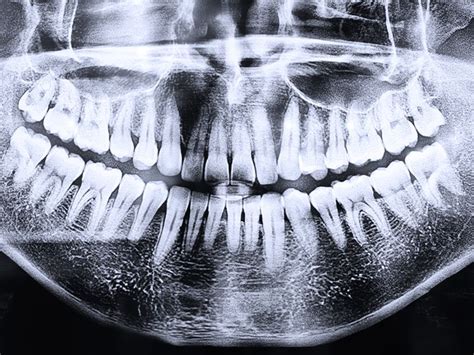

- Radiografías panorámicas: Ofrecen una vista general de todos los dientes, los maxilares y las estructuras circundantes.

Ventajas y aplicaciones de la radiografía panorámica: La radiografía panorámica es útil para evaluar el desarrollo dental, detectar quistes y tumores, y planificar tratamientos de ortodoncia e implantes.